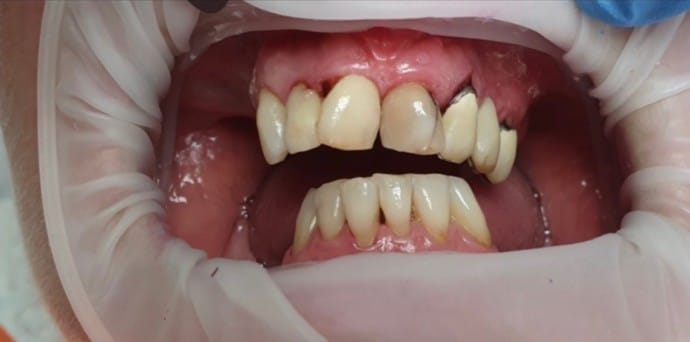

- Príprava pred nasadením koruniek (ošetrenie kazov, endodoncia a dentálna hygiena)

- Samotná príprava a brúsenie zubov

- Zhotovenie dtlačkov (digitálnych alebo pomocou odtlačkových hmôt)

- Nasadenie dočasných koruniek pre ochranu obrúsených zubov

- V poslednom kroku dochádza ku skúške a lepeniu zirkónových koruniek